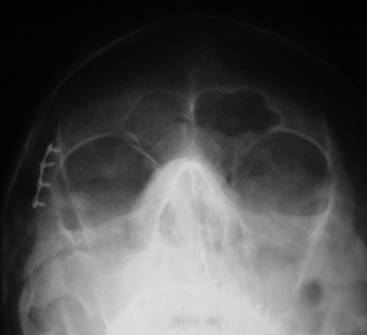

Paralelamente a los exámenes periciales, las investigaciones policiales revelaron que la probable víctima sería un hombre de 29 años, que había sido secuestrado hacía 7 meses. Además, fue remitida documentación AM, consistente en una ficha médica y dos radiografías posteroanteriores (PA) de cráneo (prequirúrgica y posquirúrgica inmediata), efectuadas 7 años antes de su desaparición, donde constaban una fractura y una placa de osteosíntesis en la región periorbitaria derecha. En las mismas, también se puso de manifiesto la morfología del seno frontal, que se presentaba expandido a ambos lados de la línea media (Fig. 3).

Se decidió, entonces, efectuar exámenes PM, una radiografía PA y una tomografía de haz cónico craneales (Fig. 4), en un laboratorio radiológico que tiene convenio con el IML. A partir de la manipulación de la tomografía PM y por medio del software InVesalius®, se reconstruyó, rotó y dispuso la imagen craneal procesada, en la misma posición que la radiografía PA posquirúrgica inmediata AM.

Paso seguido, se comparó la radiografía PA posquirúrgica inmediata AM con la radiografía PA y tomografía PM, verificándose similitud morfológica del seno frontal, en lo que refiere a su área de expansión, número y ubicación de los septos y lóbulos (Tabla 2) y de la placa de osteosíntesis presente en la pared lateral de la órbita derecha, en lo concerniente a su localización anatómica, tipo y tornillos para su fijación (cantidad, diseño y longitud, disposición y angulación de fijación), tal cual se advierte en la Fig. 5. De este modo, fue posible arribar a una identificación positiva de la persona desaparecida.